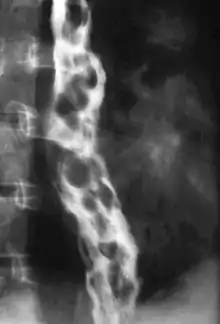

Varice œsophagienne

Le diagnostic se fait par endoscopie digestive haute, on retrouve un aspect de cordons bleuâtres, saillants, au niveau de la partie inférieure de l’œsophage.

Grade I : varices petites, frêles, pouvant s'écraser sous la pression modérée de l'insufflation de l'endoscope

Grade II : varices ne pouvant pas s'écraser sous l'insufflation de l'endoscope

Grade III : varices confluentes, quasi-circonférentielles

NB : Seules les varices de grade II et III peuvent subir une rupture avec hémorragie interne